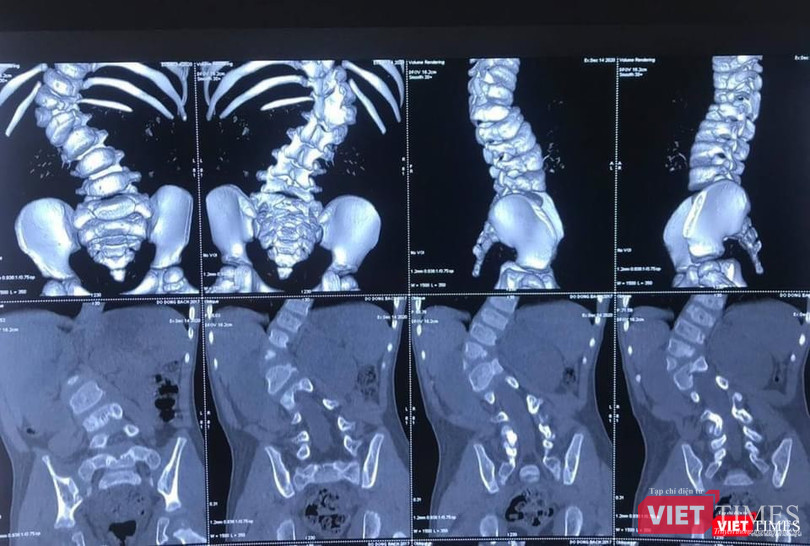

Năm nay bé 3 tuổi, tình trạng biến dạng cột sống của bệnh nhi B.Đ đã là mức độ nặng, góc vẹo 66 độ. BS chuyên khoa chẩn đoán cho biết nếu trì hoãn mổ, đến khi bệnh nhi được 6 tuổi trở lên thì sẽ không thể phẫu thuật nắn chỉnh được dị tật vẹo cột sống, nguy cơ bệnh nhi sẽ mất đi cả cuộc sống bình thường. Vi thế, bố mẹ bé đã quyết định đưa bé nhập viện vào khoa Chấn thương - Chỉnh hình Cột sống (Bệnh viện 108).

Bác sĩ chuyên khoa cho biết vẹo cột sống bẩm sinh là biến dạng vẹo của cột sống do sự phát triển bất thường của cột sống ngay từ khi trẻ em sinh ra. Hai nguyên nhân chính của vẹo cột sống bẩm sinh là bất thường về sự phân chia đốt sống, bất thường về hình thành đốt sống hoặc kết hợp cả hai nguyên nhân. Mức độ tiến triển biến dạng gù vẹo cột sống rất dao động tùy theo vị trí đốt sống phát triển bất thường. Một số trẻ có đường cong vẹo ổn định và không thay đổi theo thời gian, trong khi đó có trẻ em biến dạng vẹo tiến triển không ngừng.

| Hình ảnh X quang ca cong vẹo cột sống của bệnh nhi 3 tuổi (BVCC) |

Về mặt phẫu thuật, đây là trường hợp cháu bé còn rất nhỏ tuổi nhưng đã có biến dạng cột sống rất lớn, góc vẹo cột sống T11-L2 66 độ, có dị tật nửa thân đốt L1 bên phải, thiểu sản cuống sống T12 bên phải. Do vậy, tính chất cuộc phẫu thuật rất phức tạp.